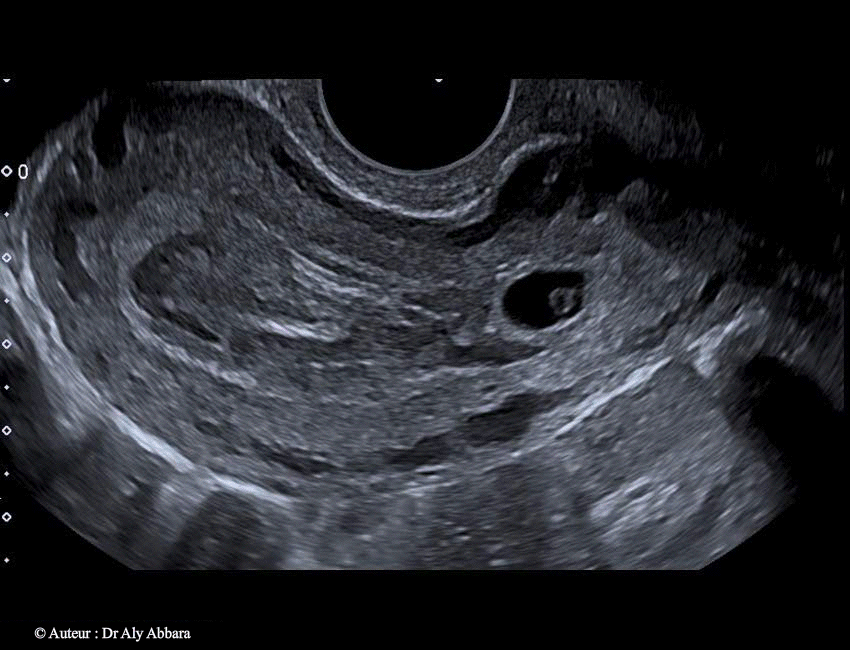

• Images échographiques montrant l'évolution spontanée d'une grossesse débutante à insertion basse, dans la zone isthmique de la cavité utérine (grossesse isthmique utérine).

• Échographiquement on peut observer à travers les images ci-dessus que le sac gestationnel qui s'est implanté dans la région isthmique de la cavité utérine continue à évoluer lors du contrôle, à 2 jours et à 4 jours après l'examen initial, avec l'apparition d'une image embryonnaire munie d'une activité cardiaque et mesurant, à J4, 2,3 mm.

Le sac gestationnel était partiellement décollé au niveau de son pôle supérieur dès l'examen initial. Ce décollement s'élargissait à J2 et à J4 ; il est à l'origine (dès l'examen initial) de la formation d'une hématométrie qui s'aggravait au cours du développement de la grossesse (36 ml à J4 et 47 ml à J6) ; deux éléments participaient à sa formation : le décollement progressif du sac gestationnel et l'effet de bouchon exércé par ce sac sur le canal cervical en l'obstruant au niveau de son orifice interne.

A J6 : on observe l'arrêt de l'activité cardiaque embryonnaire et l'écrasement du sac gestationnel et son engagement partiel dans le canal cervical sous l'effet des contractions utérines et la pression exercée par la volumineuse hématométrie.

à J10, l'utérus a été vidé de son contenu par une révision utérine.